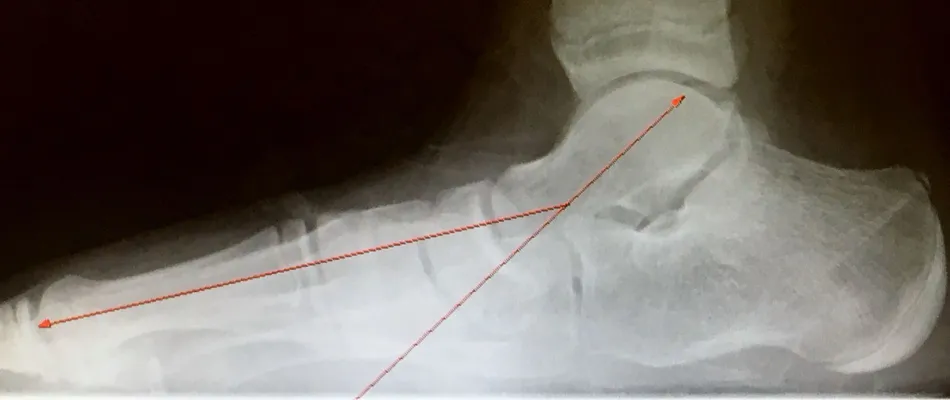

Pre-operative x-rays of the flatfoot with the talus deviated medially due to subluxing off the calcaneus causing the midtarsal joint to sublux laterally and uncovering of the talar head at the talo-navicular joint (left). The talus bone should line up with or be close to paralletl with a line drawn through the 1st metatarsal shaft (right). This is referred to as Meary's angle.

One case see an improvement in Meary's angle after surgical repair of the flatfoot with a subtalar joint implant which blocks the subluxation of the talus off of the calcaneus.